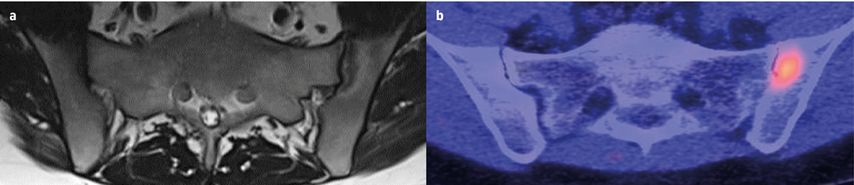

Abb. 2: Die im MRT (a) detektierten Gelenksschädigungen korrelieren mit der Signalintensität im FAPI-PET-CT (b). MRT-Läsionen ohne Gelenksschaden liefern hingegen kein Signal im FAPI-PET/CT

Inwieweit diese präklinischen Befunde auf den Menschen übertragbar sind, untersuchten Ramming und seine Mitarbeiter in einer rezenten Arbeit.5 In die Studie wurden 20 Patienten mit rheumatoider Arthritis (RA), 50 Patienten mit Psoriasisarthritis (PsA) und 50 Patienten mit axialer Spondyloarthritis (SpA) eingeschlossen. Zunächst wurden mittels FAPI-PET-CT Gewebereaktionen in verschiedenen anatomischen Regionen visualisiert (Hüftgelenksynovitis, Sakroiliitis, Tendinitis, Ellenbogenenthesitis, Facettengelenkassoziationen, Daktylitis). Bemerkenswert ist, dass die Intensität der FAPI-PET-CT-Signale mit den jeweiligen klinischen Scores (DAPSA bei PsA, SPARCC bei Enthesitis, DAS28 bei RA und PsA, ASDAS und BASDAI bei SpA) korrelierte.

In einem nächsten Schritt wurden die Probanden einer FAPI-PET-CT sowie einer MRT unterzogen. Die im MRT detektierten Läsionen wurden systematisch kategorisiert in 1. erosive Schädigungen, 2. osteoproliferative Schädigung bzw. 3. Entzündung ohne Hinweis auf eine Schädigung. Und tatsächlich zeigte sich, dass die im MRT detektierten Gelenksschädigungen mit einer erhöhten FAPI-PET-Signalintensität assoziiert waren, während Läsionen, die lediglich eine Inflammation ohne Gelenksschaden zeigten, kein FAPI-PET-Signal lieferten.